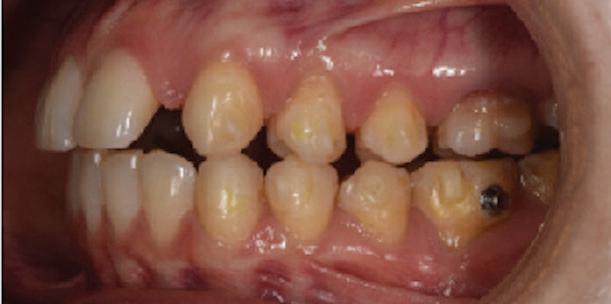

Пациентът постъпи в моята клини ка с наличие на темпоромандибуларен дисфункционален болков синдром, едно странно изместен диск с редукция в дяс ната става, клас II, подклас 2, тесни гор на и долна челюст със струпване, дъл бок овърбайт

6 Dental Tribune Bulgarian Edition / октомври 2022 г. КРАТКО ОПИСАНИЕ НА КЛИНИЧНИЯ СЛУЧАЙ

оклузална равнина ендодонтски проблеми – 15, 25, 35, 36, 37, 45, 46, 47 отклонение на срединната линия с 2 мм вляво в долна челюст мускулни болки ДИАГНОСТИКА: скелетен клас II зъбен клас II функция: ограничения в движенията –мускулни проблеми; хлабави лигамен ти – латеротрузивни странични про блеми при медиотрузия вдясно; девиа ция на долната челюст вляво. ЦЕЛИ НА ЛЕЧЕНИЕТО: разширяване на горната и долната зъбна дъга промяна на оклузалната равнина в по сока надолу – намаляване на наклона на оклузалната равнина, така че да стане по-плоска, и постигане на пра вилна оклузална равнина дистално намаляване на вертикалния размер на оклузията (LFH)

и гингивална усмивка. Започнахме лечението с пълна диагно стика (анамнеза, интраорални, екстра

7Dental Tribune Bulgarian Edition / октомври 2022 г. Преди лечението Фиг. 1 Фиг. 4 Фиг. 7 Фиг. 10 Фиг. 13 Фиг. 16 Фиг. 17 Фиг. 18 Фиг. 19 Фиг. 20 Фиг. 11 Фиг. 14 Фиг. 12 Фиг. 15 Фиг. 8 Фиг. 9 Фиг. 5 Фиг. 6 Фиг. 2 Фиг. 3

8 Dental Tribune Bulgarian Edition / октомври 2022 г. По време на лечението Фиг. 21 Фиг. 25 Фиг. 30 Фиг. 31 Фиг. 34 Фиг. 38 Фиг. 40 Фиг. 44 Фиг. 48 Фиг. 50 Фиг. 49 Фиг. 46 Фиг. 39 Фиг. 41 Фиг. 45 Фиг. 47 Фиг. 42 Фиг. 43 Фиг. 35 Фиг. 36 Фиг. 37 Фиг. 32 Фиг. 33 Фиг. 26 Фиг. 28 Фиг. 29 Фиг. 27 Фиг. 22 Фиг. 23 Фиг. 24